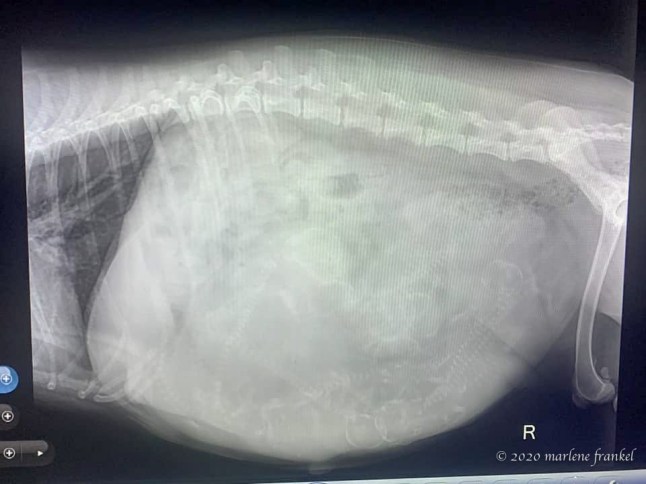

Starting on February 2 my pup to be mama Ginger moved to Jo’s house in preparation for her upcoming birth of puppies. After an ultrasound Jo let me know that even though I am 5 or 6th on list Ginger was puppy full. My guess was 9 or 10.

Puppy Full (ultrasound)

Our preference is for a solid colored girl, but I will happily enjoy having a boy. Well On February 7th Ginger’s labor started. Grand total many hours later is 10 puppies – 7 boys and 3 girls.